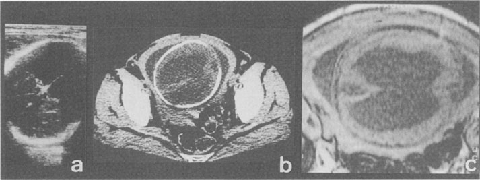

In order to evaluate the structual brain reconstitution and functional recovery, clinical record of an infant presenting hydrocephalus in utero at 31 weeks of gestation and operated immediately after birth was reported. Before the advent of sonography, the diagnosis of fetal hydrocephalus was based on the radiologic demonstration of an enlarged fetal head. With the propagation of B-mode ultrasound imaging in the obstetrical field, pathological ventriculogram could be diagnosed antenatally. In this case, greatly distended hydrocephalic brain regressed completely by continuous cerebrospinal fluid drainage through a miniature Ommaya’s reservoir during early neonatal period and thereafter ventriculoperitoneal shunting at age of four weeks after birth. Also, electroencephalogram at age of 35 days showed improvement as disappearance of high-voltage slow wave on the frontal region and the normal pattern corresponding to his moon’s age. This paper reviewed the current understanding of diagnosis and prognosis of fetal hydrocephalus, and author’s opinions for neurosurgical management early after birth are stated.